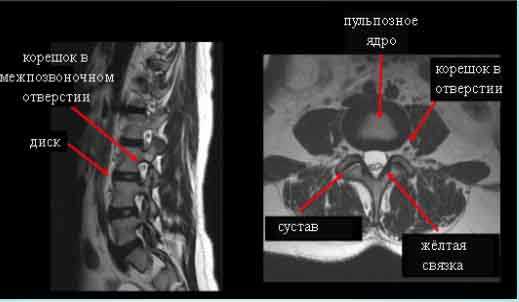

(Слева) Т1-ВИ, аксиальная проекция: деформация и вентральное смещение спинного мозга. Во время операции у данного пациента, у которого наблюдался прогрессирующий нижний парапарез, было подтверждено наличие дефекта дурального мешка.

(Справа) Т2-ВИ, сагиттальная проекция: фокальная деформация и вентральное смещение спинного мозга, достигающего задней поверхности тела позвонка. Дифференциальный диагноз включает заднюю арахноидальную кисту и грыжу спинного мозга.